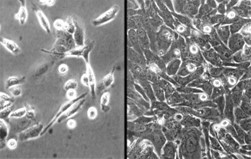

◆肝癌细胞系-HuH-7(JCRB0403)

| ● 可在无血清和无蛋白条件下培养 ● 易于基因转移 ● 优异的差异化功能 ● 细胞来源:肝癌(分化型),57岁,男性,细胞系建立于1982年 参考文献 Pubmed id:10390360 Replication of subgenomic hepatitis C virus RNAs in a hepatoma cell line. Lohmann V, Körner F, Koch J, Herian U, Theilmann L, Bartenschlager R Science. 1999 Jul 2;285(5424):110-3 |